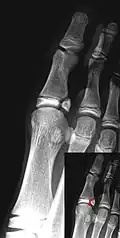

Salter–Harris I fracture of distal radius. -

Salter–Harris II fracture of ring finger proximal phalanx. -